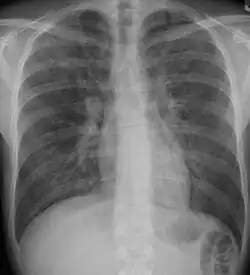

Pneumocystis pneumonia can present with interstitial lung disease, as seen in the reticular markings on this AP chest x-ray.

A chest X-ray demonstrating pulmonary fibrosis due to amiodarone

Diagnosis of ILD involves assessing the signs and symptoms as well as a detailed history investigating occupational exposures. ILD usually presents with dyspnea, worsening exercise intolerance and 30-50% of those with ILD have a chronic cough. On examination, velcro crackles, in which the crackles compare to the sound of velcro being unfastened, are common in ILD.[10] Pulmonary function tests usually show a restrictive defect with decreased diffusion capacity of carbon monoxide (DLCO) indicating reduced alveolar to blood capillary transport.[10] Pulmonary function testing is indicated for all people with ILD and the FVC loss and DLCO is prognostic, with an FVC loss of greater than 5% per year associated with a poor prognosis in fibrosis subtypes of ILD.[10]

A chest x-ray is 63% sensitive and 93% specific for ILD.[10] With advances in computed tomography, CT scans of the chest have supplanted lung biopsy as the preferred diagnostic test for ILD. A thoracic CT scan is 91% sensitive and 71% specific for ILD.[10] In higher income countries, less than 10% of people with ILD undergo a lung biopsy as part of the diagnostic evaluation.[16]

Chest radiography is usually the first test to detect interstitial lung diseases, but the chest radiograph can be normal in up to 10% of patients, especially early in the disease process.[19][20]